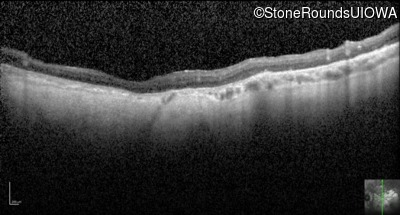

Optical Coherence Tomography - Right - 10/200 -2 sc

Exemplar / OCT Stack

OCT Stack